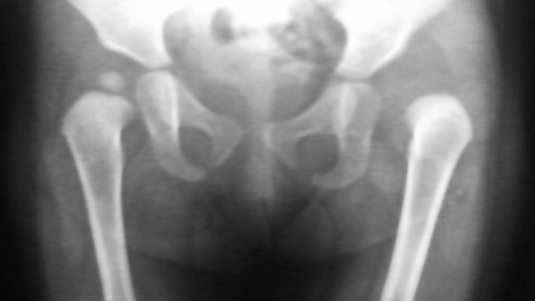

标题: PED0514双胞胎,1岁10个月,走路不稳。

老二:

有什么好的办法吗?等到2岁半手术,不手术可以吗?

先天性左侧髋关节脱位。

考虑左髋关节先性脱位。

左侧先天性髋关节脱位.

左侧先天性髋关节脱位.典型!